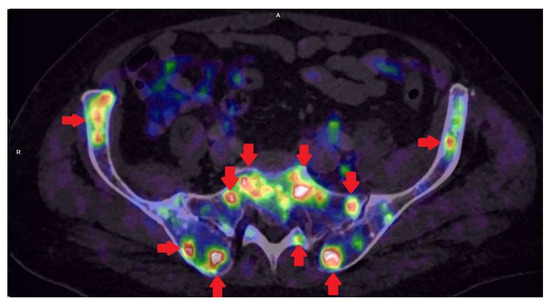

PET/CT with radiolabeled choline analogs is widely used in clinical practice for prostate cancer staging. 18F-fluoroethylcholine PET demonstrated higher accuracy than MRI for the detection of primary prostate cancer; specificity was however limited by choline uptake in benign lesions [15]. Since 2012, [18F]- and [68Ga]-labeled inhibitors of prostate-specific membrane antigen (PSMA) entered early clinical development for PET imaging of PCa and showed immediate promise for sensitive and specific identification of local and distant sites of disease [16,17]. Results from [68Ga]-PSMA-11 PET/MRI and PET/CT in Figure 2, Figure 3 and Figure 4. To summarize, according to the available systematic reviews and clinical trials, the sensitivity and specificity in primary staging of PCa using PSMA ligands is usually above 40% and over 85%, respectively. The impact on therapy planning was also investigated, performing PET/CT or, less frequently, PET/MRI using PSMA ligands, the therapeutic procedure changes in approximately 21% of patients in the primary staging [18,19].

Figure 3. Patient with lymph nodes metastases in prostate cancer GS 9 (4 + 5) iPSA 22.85 PHI 130.63 in [68Ga]-PSMA-11 PET/MRI.

Life 11 00324 g003